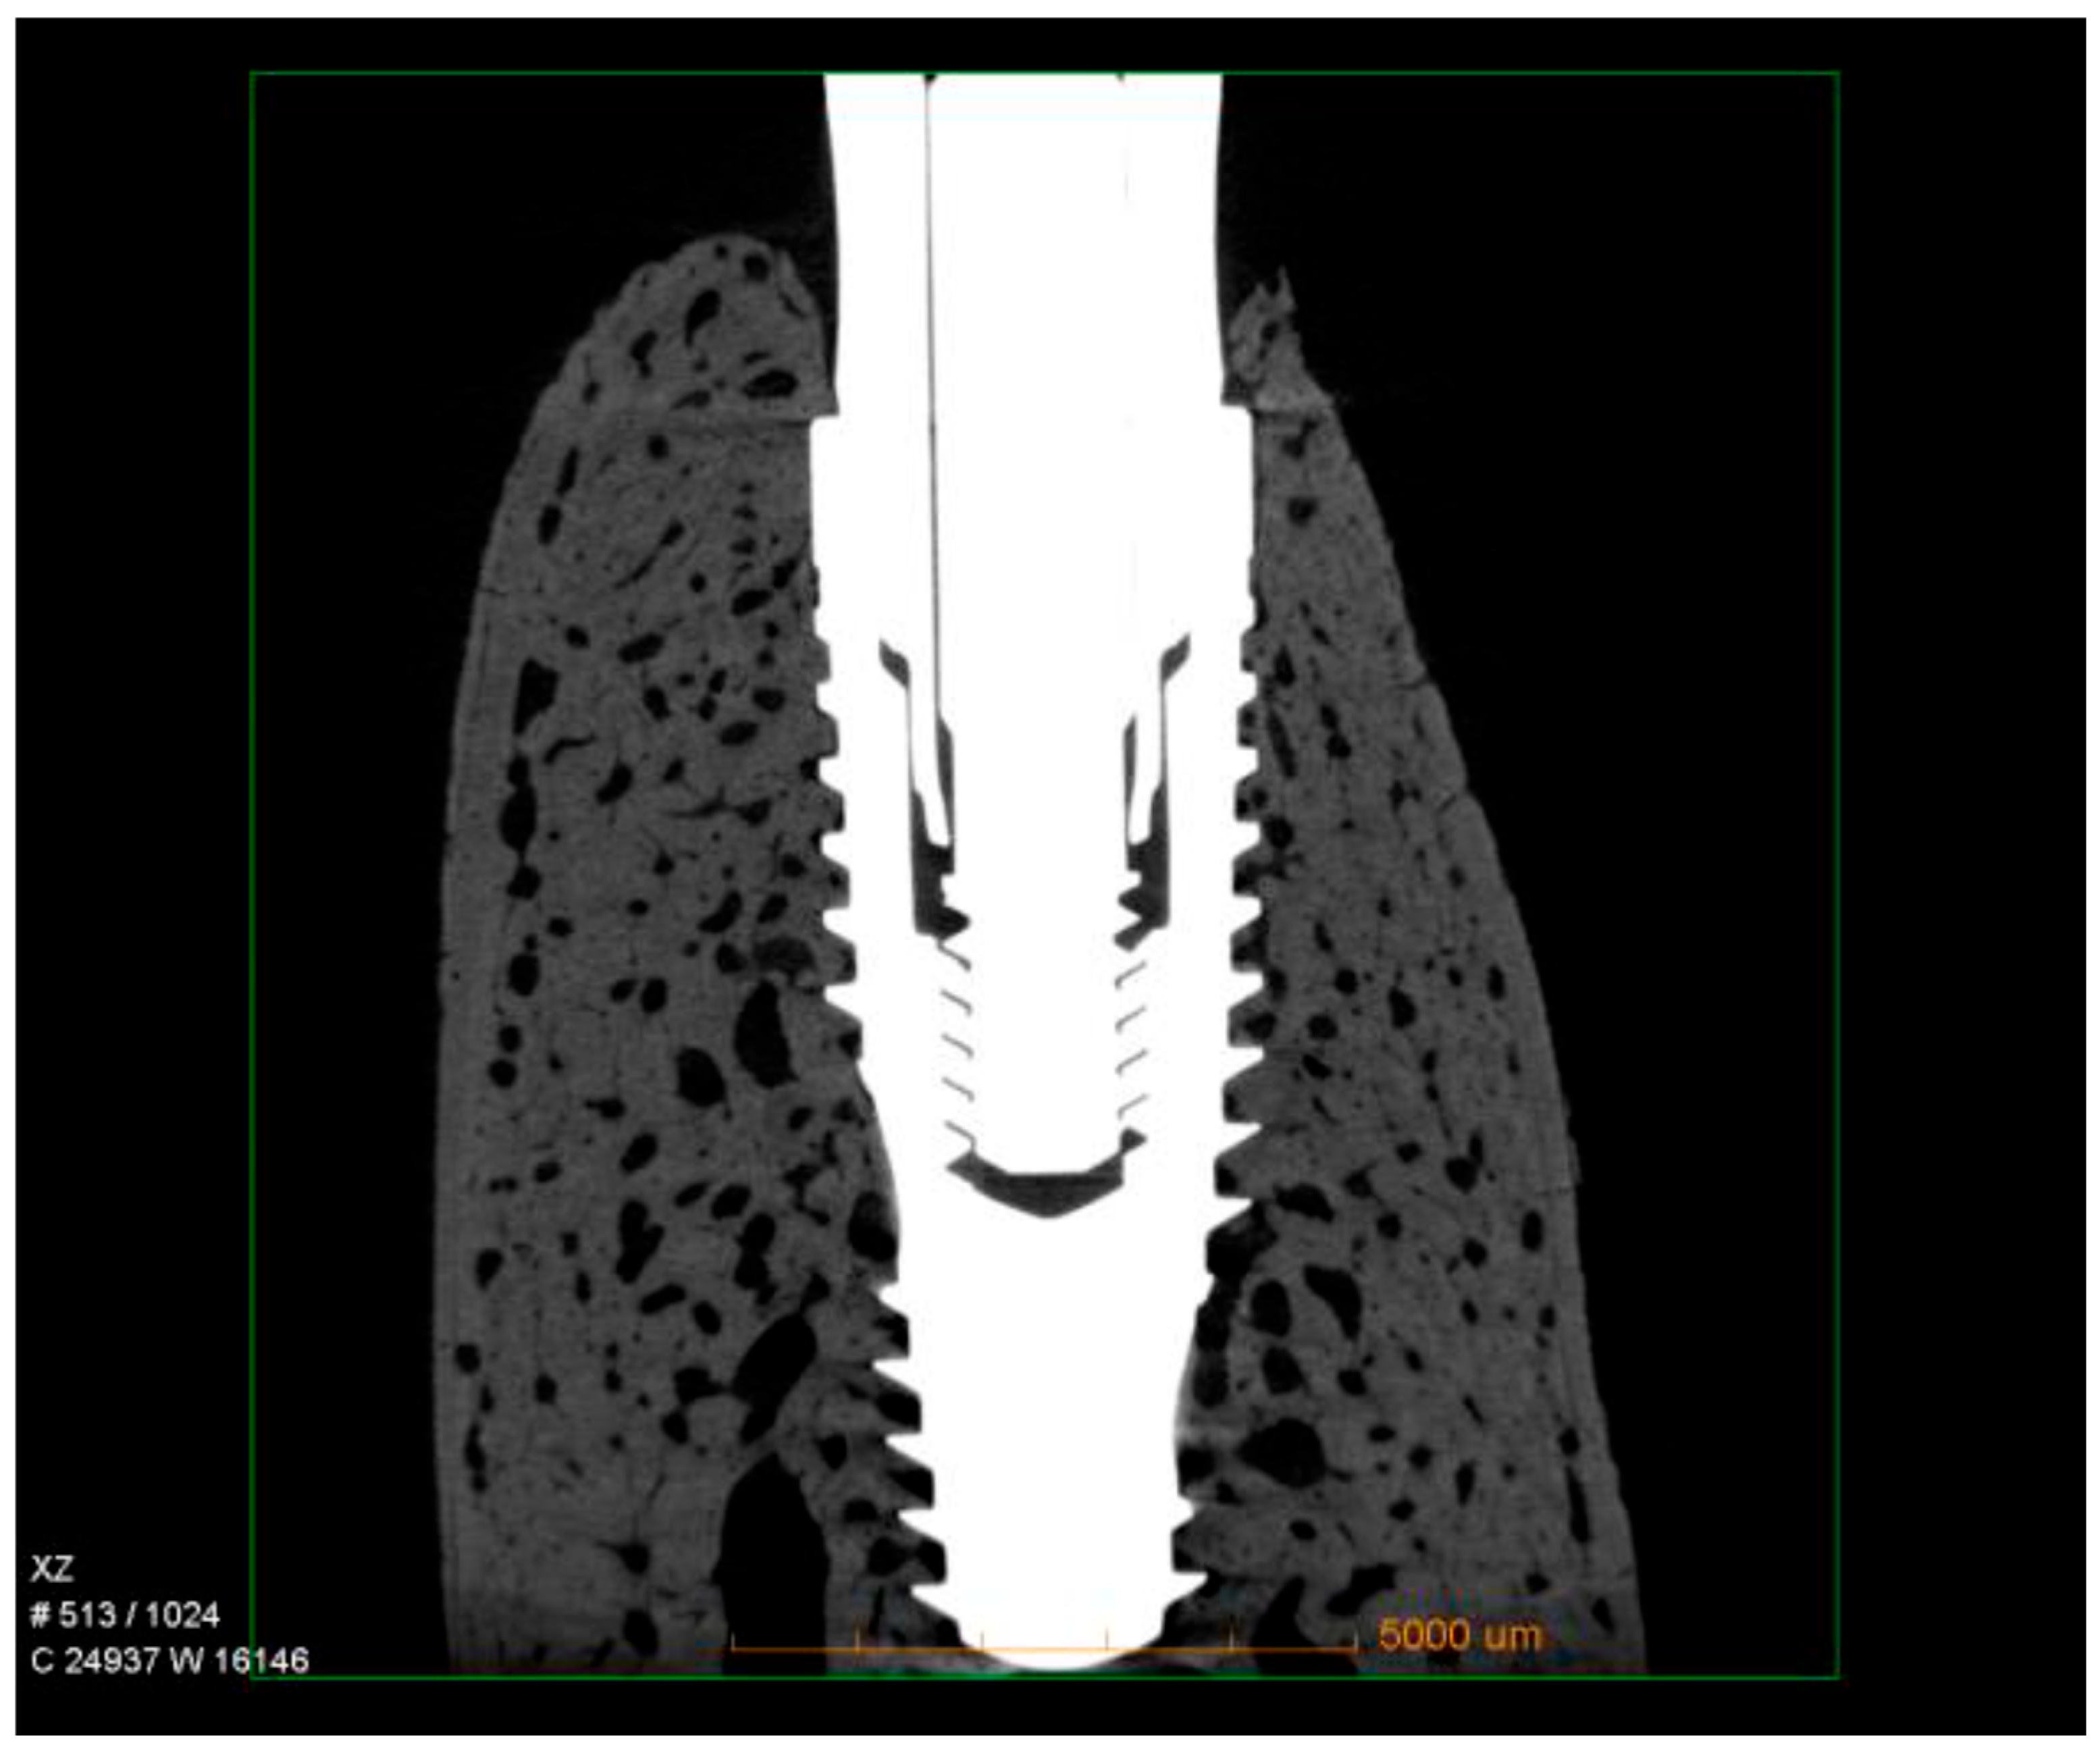

Micro-CT qualitative analysis confirmed close bone contact along the implant surface, with dense trabecular bone filling the peri-implant region. Three-dimensional reconstructions revealed that the hybrid conical implant maintained stable crestal bone levels, consistent with the histological findings. No evidence of bone resorption, marginal defects, or saucerization was observed. Instead, the peri-implant bone appeared continuous and well-integrated around the implant threads, particularly in the coronal portion, supporting the quantitative data obtained for nBIC and BT/TV (Figure 4).

Figure 4.

Representative micro-CT images of hybrid conical implants after 60 days of healing. The reconstructions show dense trabecular bone surrounding the implant surface, with preservation of crestal bone levels and no signs of marginal bone loss.